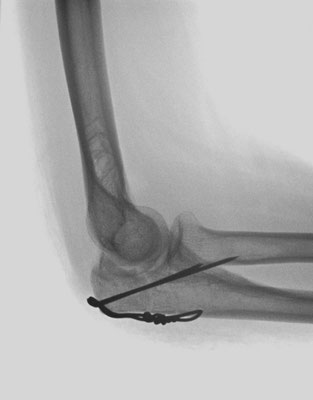

Ellenbogennaher Ellenbruch (Olecranonfraktur)

Der Ellenhaken (Olecranon) stellt den knöchernen Teil dar, über den die Kraft des Trizepsmuskels in den Unterarm geleitet wird und somit die aktive Streckung des Ellenbogens gegen Widerstand ermöglicht wird. Durch den Zug der Trizepssehne wird das kleine Knochenfragment weggezogen. Die Kraftübertragung des Muskels auf den Unterarm ist abgehängt. Insofern ergibt sich die Erfordernis, das Knochenteil und damit auch die Sehne des Trizeps wieder am Unterarm zu befestigen. Zusätzlich muss auch die Kongruenz des Gelenkes wieder hergestellt werden. Je nach dem, ob es sich um einen einfachen oder komplizierten Knochenbruch handelt, wird eine sog. Zuggurtungsosteosynthese mit zwei Drähten und einer Achterschlinge (Abb. 6a-b) oder eine Stabilisierung mit einer Platte durchgeführt.